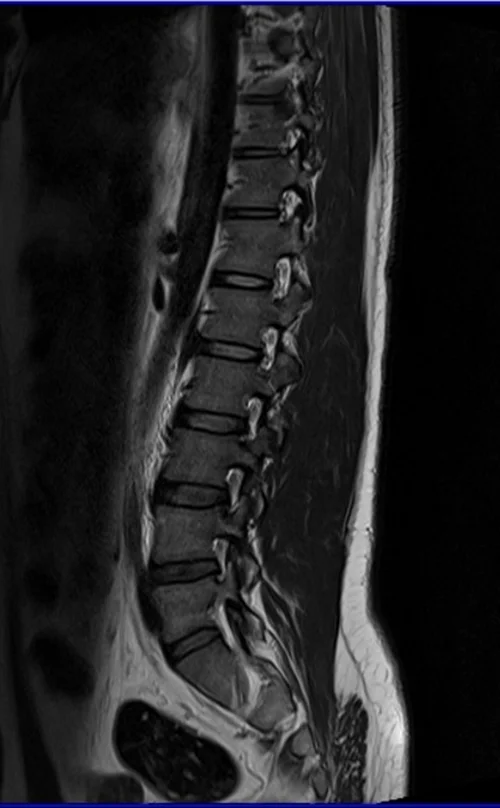

l spine sag t2 image 2 - MRI